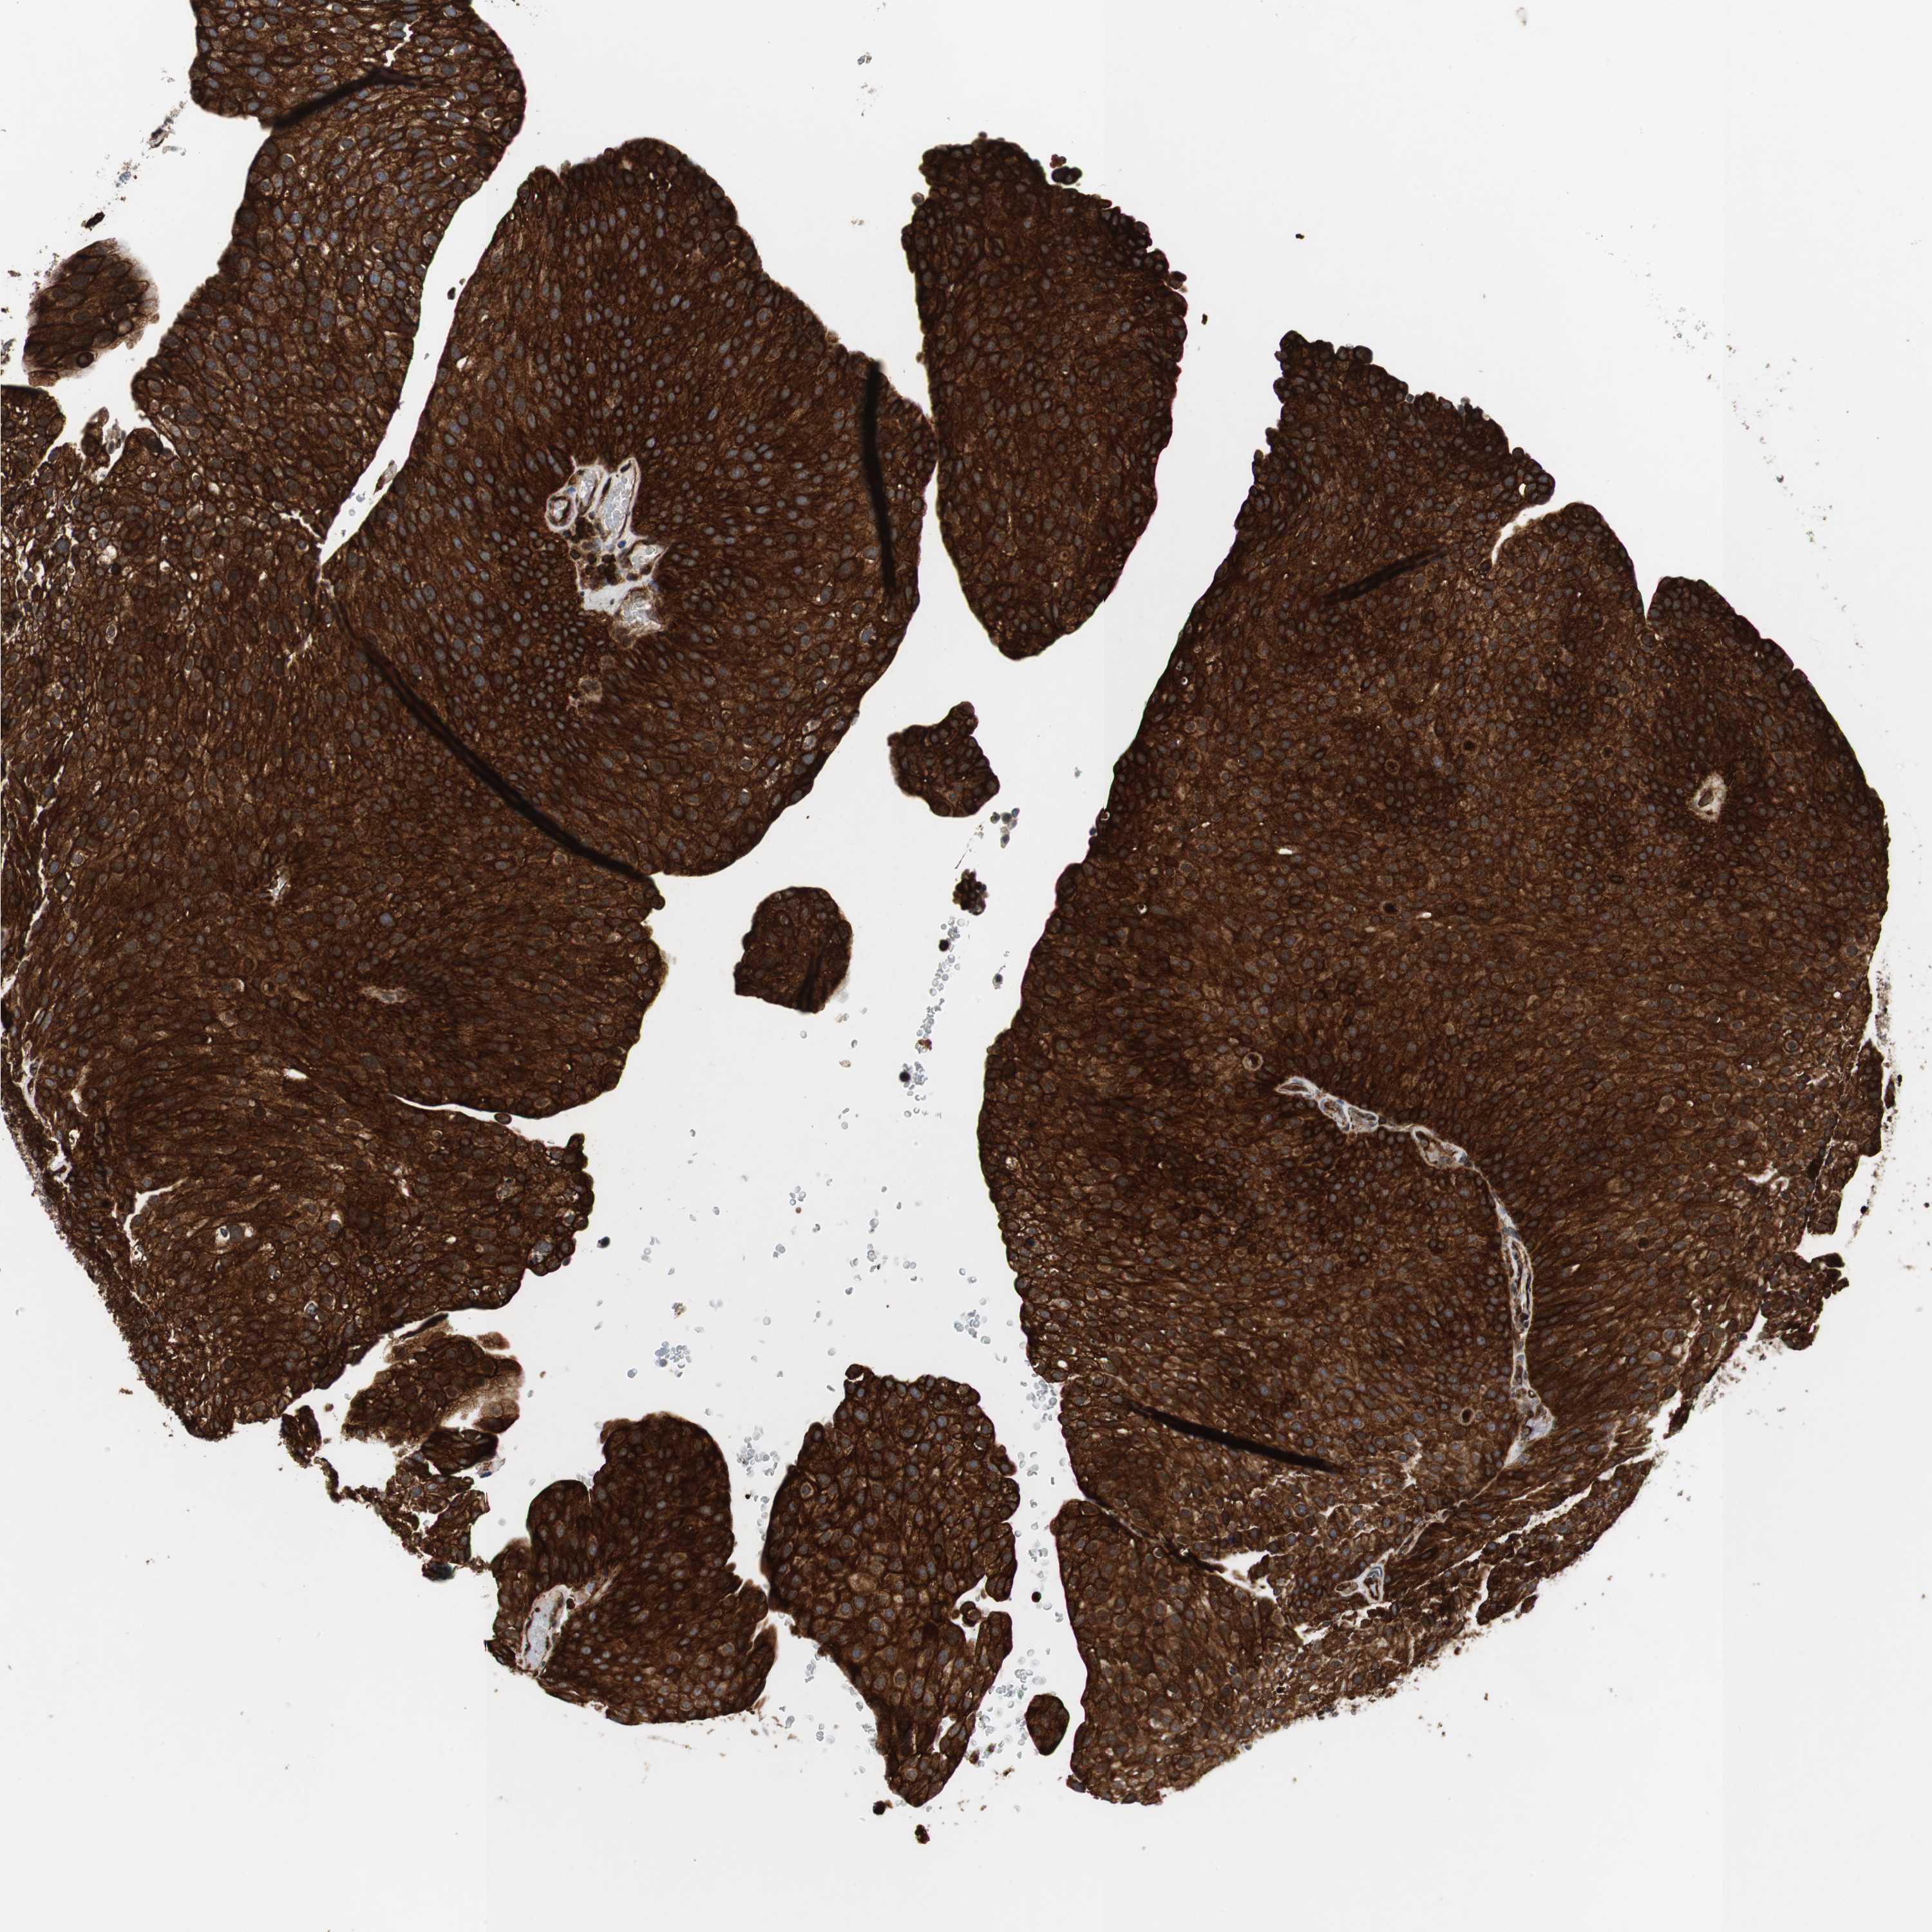

UROTHELIAL CANCER - Protein expressioni

A mouse-over function shows sample information and annotation data. Click on an image to view it in a full screen mode. Samples can be filtered based on level of antibody staining by selecting one or several of the following categories: high, medium, low and not detected. The assay and annotation is described here.

Note that samples used for immunohistochemistry by the Human Protein Atlas do not correspond to samples in the TCGA dataset.

Antibody stainingi

Antibody staining in the annotated cell types in the current human tissue is reported as not detected, low, medium, or high, based on conventional immunohistochemistry profiling in selected tissues. This score is based on the combination of the staining intensity and fraction of stained cells.

Each image is clickable and will lead to virtual microscopy that enables deeper exploration of all samples and also displays staining intensity scores, fraction scores and subcellular localization as well as patient and tissue information for each sample.

HPA039247

HPA043684

HPA063394

CAB004621

CAB005887

Staining

High

Medium

Low

Not detected

Intensity

Strong

Moderate

Weak

Negative

Quantity

>75%

75%-25%

<25%

None

Location

Nuclear

Cytoplasmic/membranous

Cytoplasmic/membranous,nuclear

Urothelial carcinoma, High grade

Urothelial carcinoma, Low grade